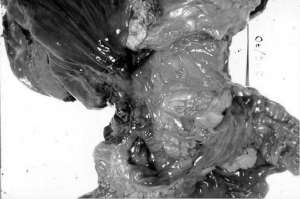

Рак и язва желудка. Язва желудка проявляется характерными синдромами. Прежде всего - жгущая или ноющая боль, очаг которой расположен между грудиной и пупком. Возникает в основном в ранние утренние часы или после приема пищи. Возможная продолжительность боли — до нескольких часов. Высокая вероятность тошноты, рвоты, потери аппетита и снижения веса.

При длительном употреблении никотина, в желудке курильщика происходит стимуляция секреции соляной кислоты, которая разъедает защитный слой полости желудка. Это становится причиной язвы, на фоне которой очень высок риск развития рака желудка. Этот рак на ранних стадиях протекает бессимптомно, поэтому его своевременная диагностика весьма сложна.